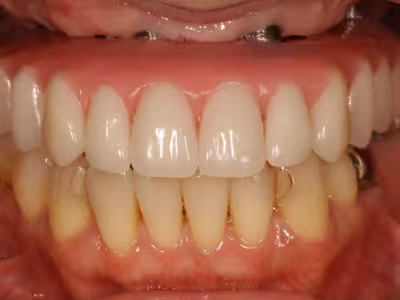

治療前後写真

治療前

治療後

年齢・性別

40代・女性

来院理由

上顎の歯が痛くて噛みにくい/見た目も気になる

治療内容

- ① CT診査・サージカルガイド作製

- ② インプラント体埋入手術+仮歯装着

- ③ 最終上部構造装着

治療期間

約18 か月

費用

3,140,500円(税込・自費診療、保険適応外)

リスク・副作用

- 術後の腫脹・疼痛・出血

- インプラントが骨結合しない可能性

- 神経損傷や上顎洞穿孔のリスク・定期メンテナンスが必要

医院コメント

噛む機能だけでなく口元のバランスも改善。

定期メンテナンスにより長期安定を目指します。